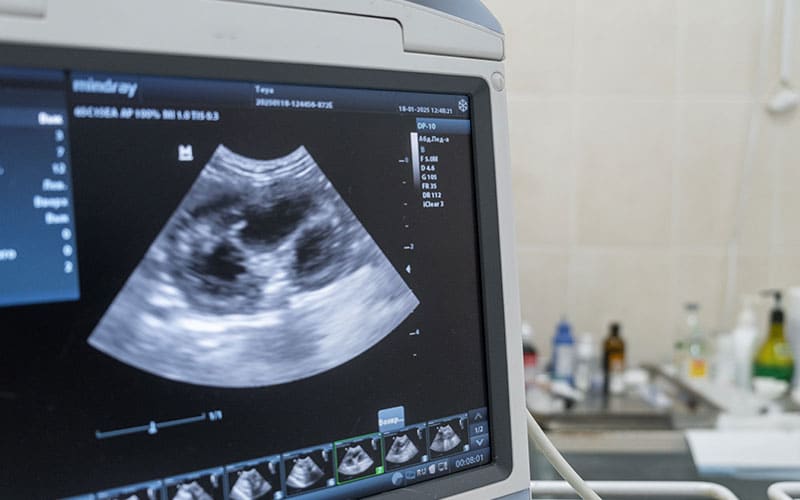

Ultrasound

Ultrasound is a non-invasive imaging technique that provides detailed, three-dimensional, real-time images of your pet’s internal organs without radiation. Our team uses ultrasound to evaluate abdominal organs, obtain biopsies, collect urine, and monitor hospitalized patients in a cost-effective manner.

Abdominal ultrasound

An abdominal ultrasound is a complete scan of your pet’s internal organs, including the liver, kidneys, spleen, bladder, adrenal glands, pancreas, gallbladder, and intestines. Non-invasive abdominal ultrasound is essential for diagnosing tumors, evaluating organ size and appearance, and obtaining ultrasound-guided needle biopsy samples. Detailed measurements and image snapshots collected during an abdominal scan are analyzed to guide us in developing a treatment plan for your furry pal’s health concerns.

Echocardiography

Echocardiography, or cardiac ultrasound, is a specialized imaging technique used to evaluate the heart’s structure and function. Echocardiography and cardiology services are essential to diagnose and monitor pet heart conditions, including cardiomyopathy, valve disorders, and congenital malformations, and ensure adequate heart function before anesthesia in pets with a heart murmur.